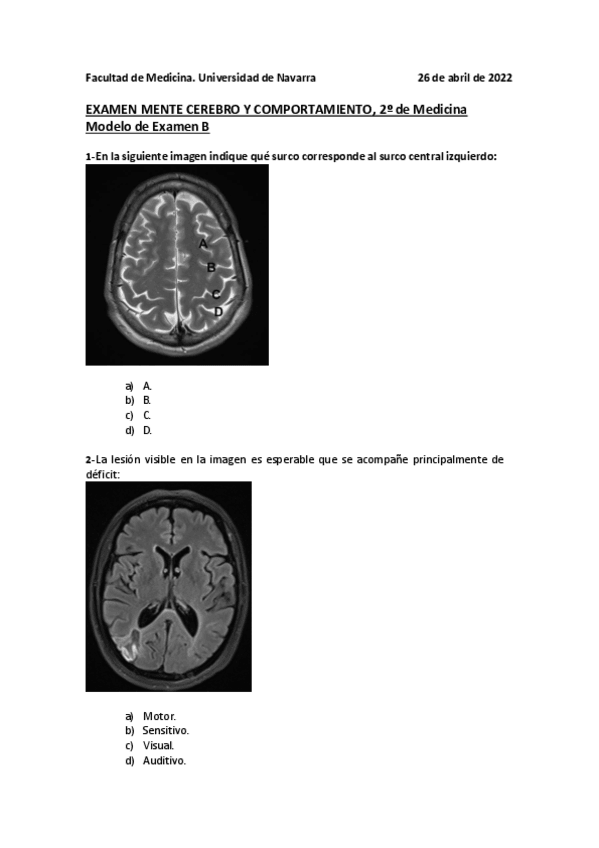

He publicado nuevos apuntes de 2º Mente, cerebro y comportamiento: MCC-PARCIAL-26-ABRIL-2022-CON-RESPUESTAS-2.pdf

15 páginas

He publicado nuevos apuntes de 2º Mente, cerebro y comportamiento: MCC-PARCIAL-26-ABRIL-2022-SIN-RESPUESTAS-2.pdf

16 páginas